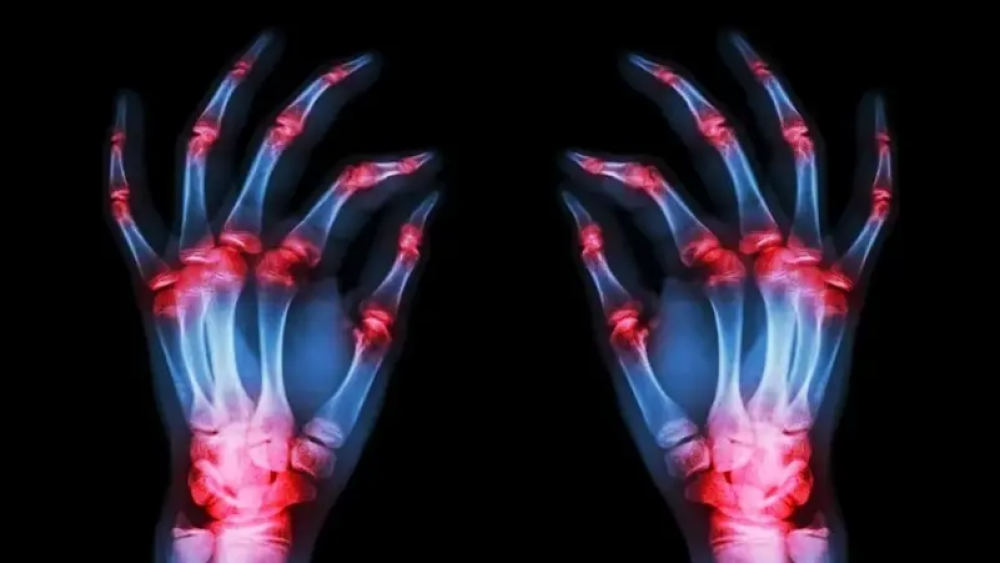

اكتشف باحثون أميركيون آلية جديدة تثبت أن بروتينا رئيسيا يتسبب في الضرر الالتهابي المرتبط بالتهاب المفاصل الروماتويدي.

ومن المأمول أن يؤدي الاكتشاف غير المسبوق إلى توجيه البحث نحو مسارات جديدة تمامًا لعلاج المرض الذي ينجم عن اضطراب في المناعة الذاتية والذي يصيب الملايين حول العالم، بحسب ما نشره موقع New Atlas نقلًا عن دورية Cellular & Molecular Immunology.

كان أحد أكثر اكتشافات التهاب المفاصل الروماتويدي تأثيرًا على مدار العقود القليلة الماضية هو العثور على السيتوكين المناعي المسمى عامل نخر الورم ألفا (TNF-alpha) والذي يلعب دورًا حاسمًا في التهاب أنسجة المفاصل. بعد هذا الاكتشاف، أتاح تطوير مثبطات TNF للأجسام المضادة أحادية النسيلة لمرضى التهاب المفاصل الروماتويدي نوعًا جديدًا تمامًا من الأدوية لعلاج حالتهم.

ركز البحث الجديد على نوع من الخلايا البشرية يسمى الخلايا الليفية الزليلية، والتي تبطن المفاصل، وفي حالات التهاب المفاصل الروماتويدي، يتم تحفيز الالتهاب في الخلايا الليفية الزليلية بواسطة TNF alpha.